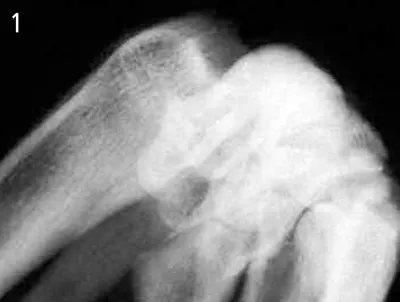

Diagnosis. The standard dorsopalmar, mediolateral, mediolateral flex, and dorsopalmar oblique radiographic views were not diagnostic; however, the palmaromedial dorsolateral hyperflexed oblique view identified a short fracture line with a subchondral defect affecting the dorsal articular margin of the radius (Figure 1). A skyline view (Figure 2) confirmed the diagnosis and established the exact location and size of the bone fragment.

In this case, open reduction and rigid, "gap-free" internal fixation was performed. The fracture was exposed with a small incision made directly between the extensor carpi radialis and the common digital extensor tendons. The fragment was reduced and fixed with a 1.5-mm lag screw (Figure 3). The head of the screw was countersunk to avoid irritation of the surrounding soft tissues or interferences with the proximal carpal bones during extension of the joint. After the surgery a light bandage was applied to the carpus for 10 days. After suture removal, a light bandage was reapplied for another 7 days and light exercise and physiotherapy were encouraged. Eight weeks after surgery, radiographs showed signs of bone healing. Ten weeks after the surgery, Sophie was back to full activity.